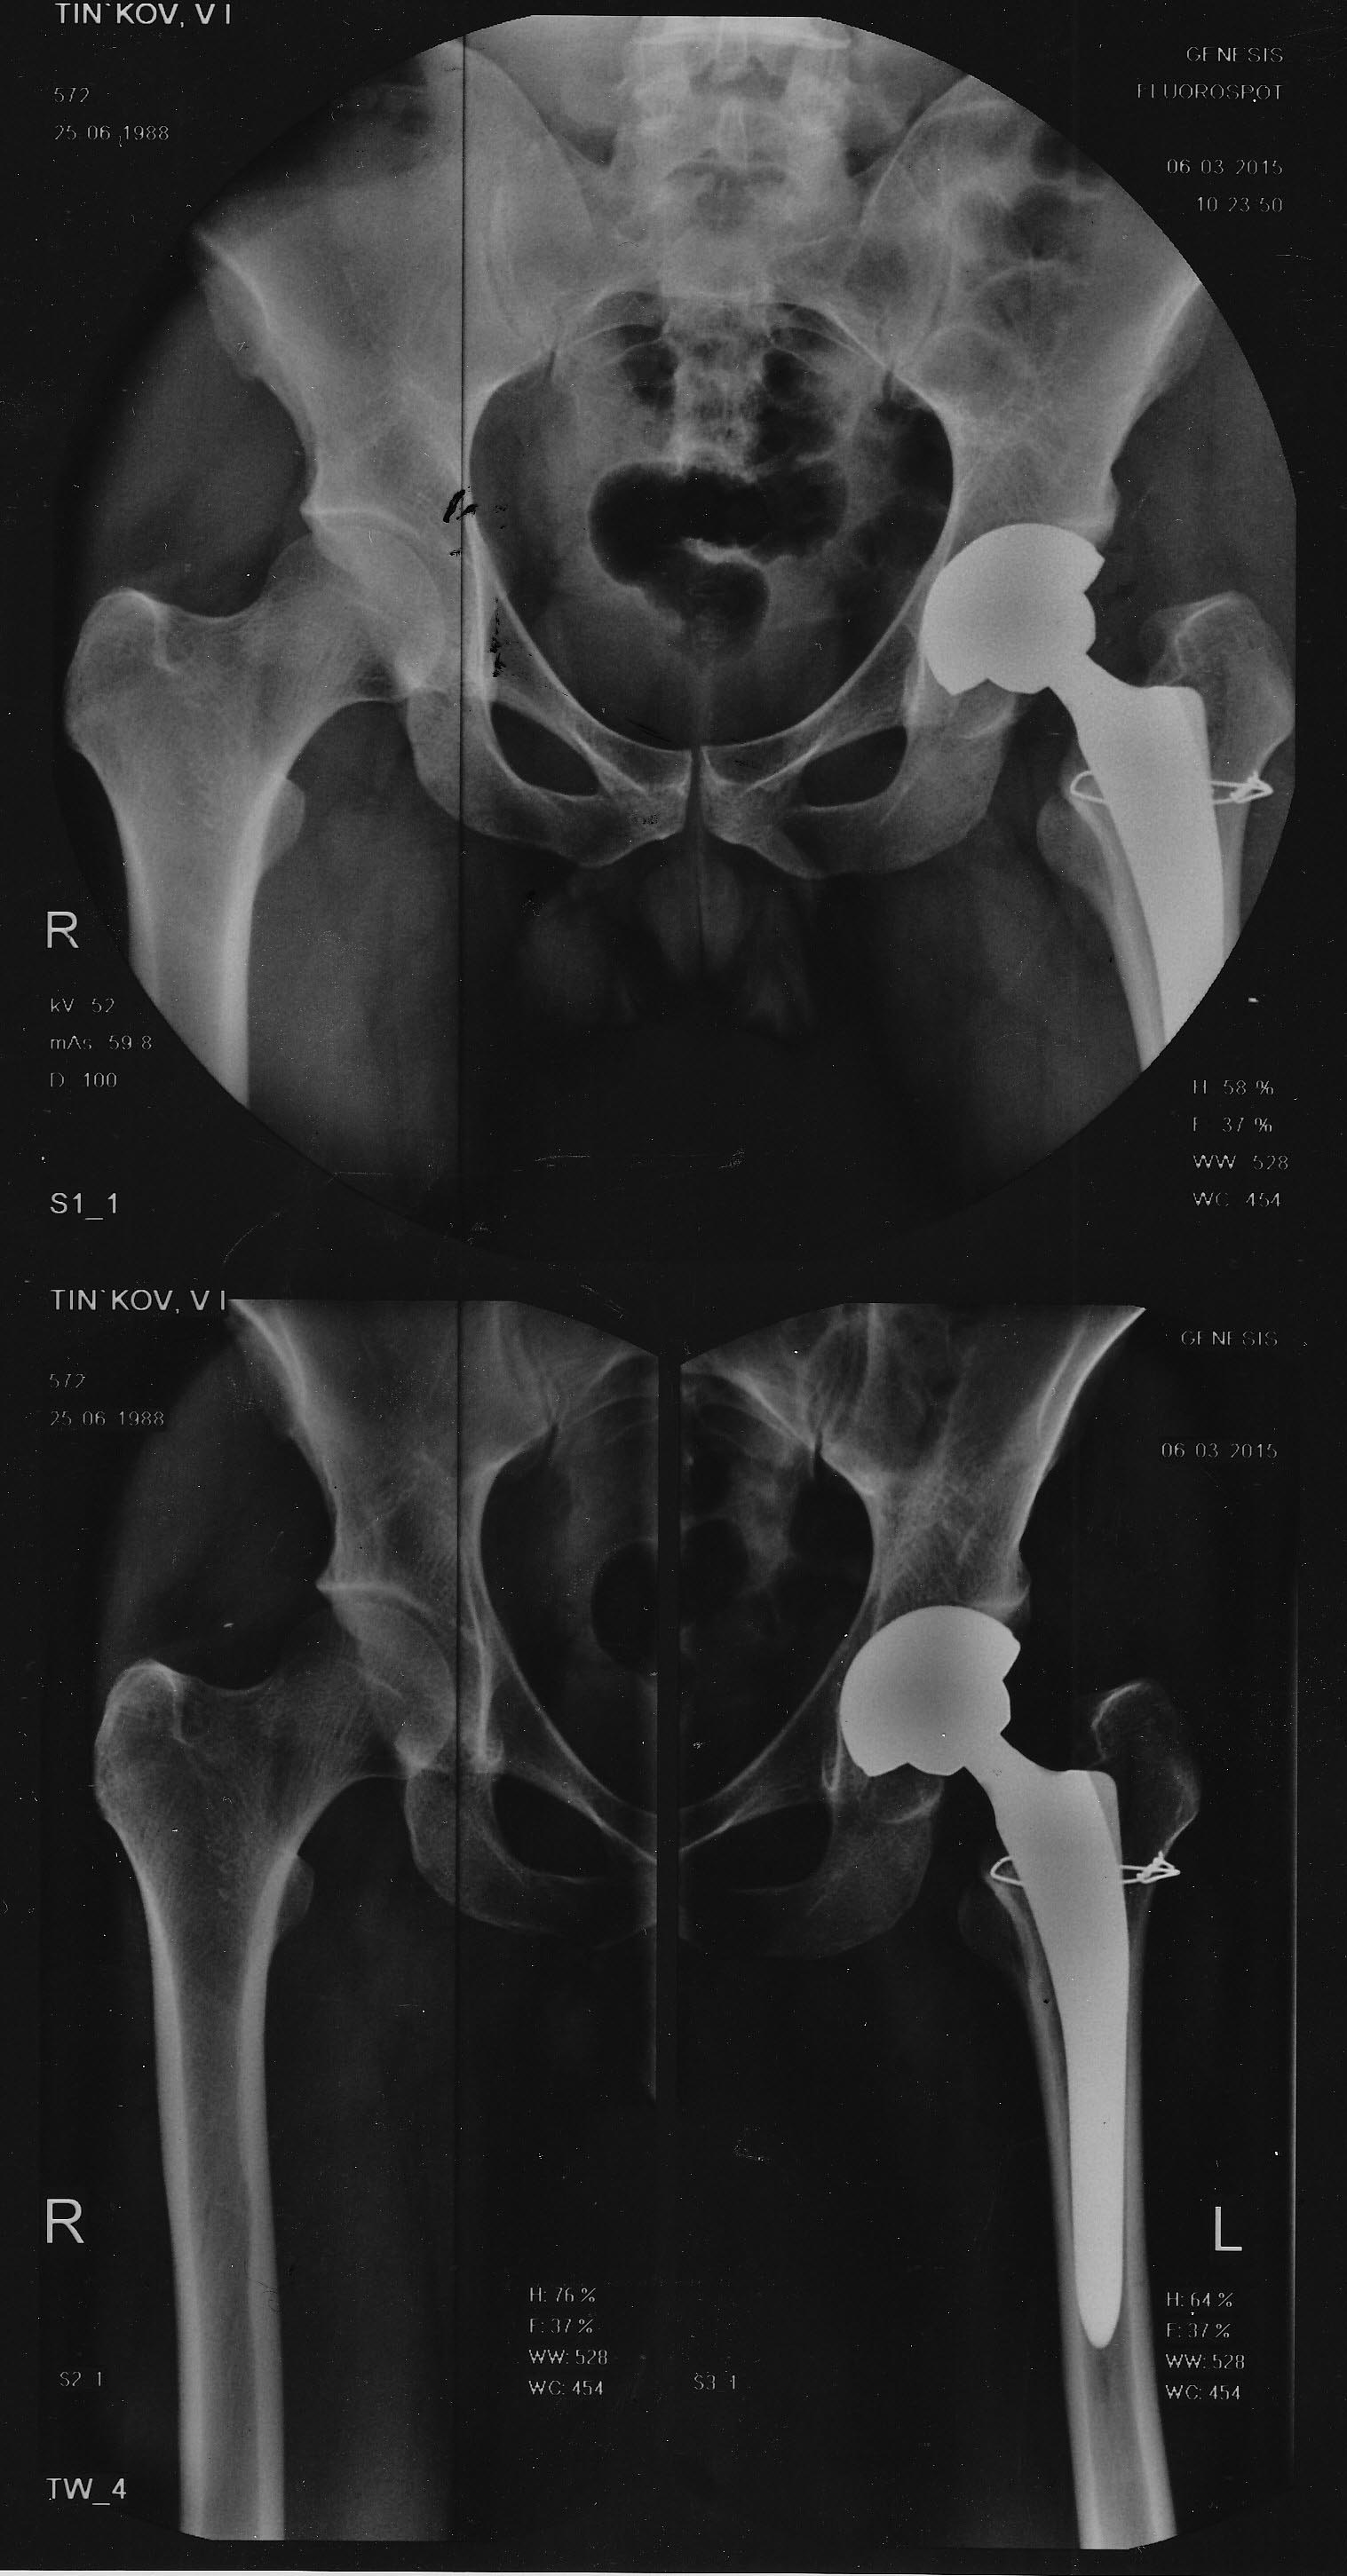

здравствуйте, выкладываю рентгенограммы, прошу прощения за отсутствие

предоперационных снимков. выложить смогу только во вторник.